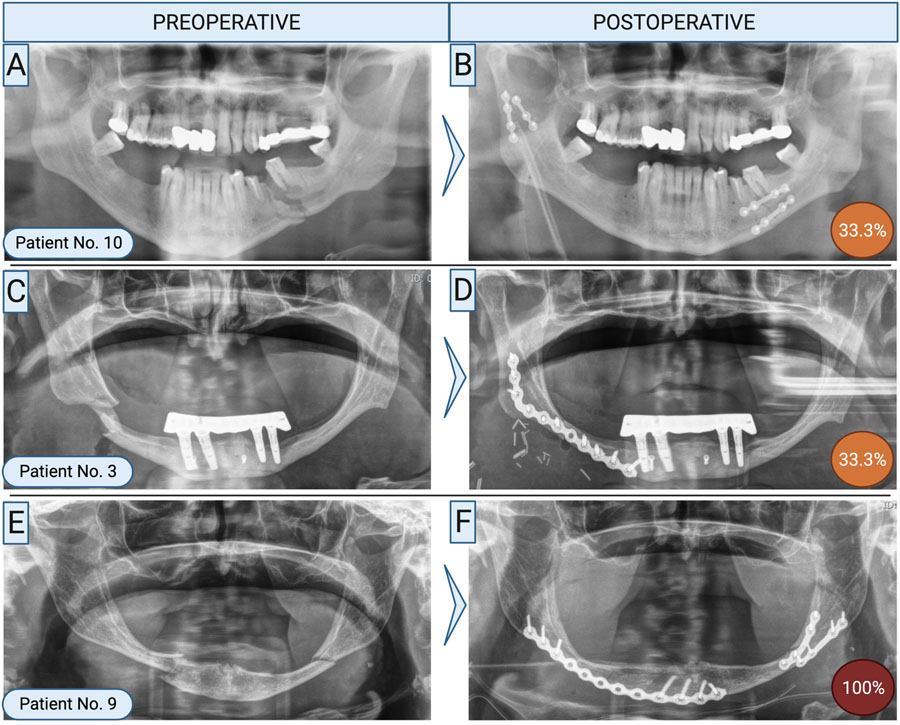

How was refixation performed?

Refixation was typically prompted by complications such as osteomyelitis or non-union, both of which demanded more invasive surgical approaches. In 82% of cases, an extraoral approach was used, employing load-bearing osteosynthesis techniques. Reconstruction plates were the most common fixation method—47% involved conventional plates, while 41% utilized patient-specific, 3D-printed plates.

Bone grafting from the iliac crest was necessary in about 30% of cases. Intraoral soft tissue conditions likely played a role in the surgical decision-making process, as successful grafting depends heavily on infection-free closure and adequate healing.